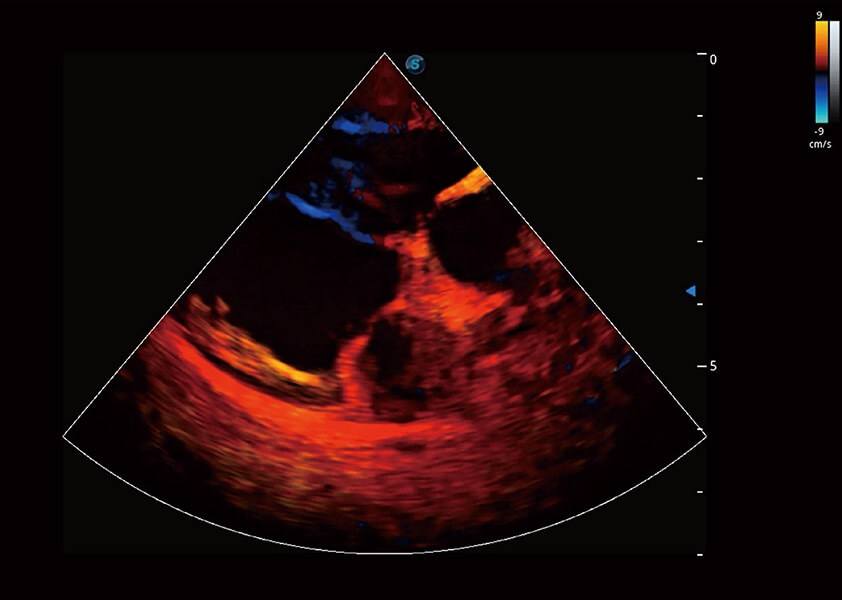

ProPet 60 作为一款高端台式动物超声设备,为动物医生的日常诊断提供了一系列贴合动物临床需求、解决临床实际问题的高级成像功能。凭借全系列高清探头,满足医生对腹部、心脏、生殖、浅表、肌骨等成像的所有需求,切实帮助您提升检查效率,提高诊断信心。

兽用彩色多普勒超声诊断系统

动物是人类最亲密的朋友和最值得信赖的伙伴。亚星官网也一直致力于探索动物专用的超声影像解决方案。 全新推出的ProPet系列,是亚星官网在动物超声影像智能化、专业化、精准化的一次跨越式革新。动物不能用言语来表述自己的不适,通过超声影像,ProPet系列搭建了动物医生与不同物种沟通的“桥梁”,为动物医生注入了“治愈之力”。